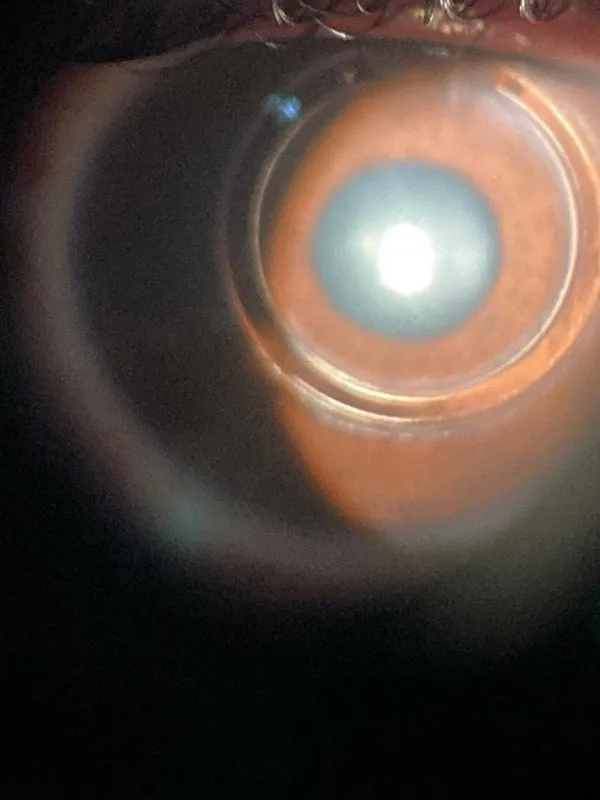

O ceratocone é uma doença de etiologia multifatorial, com componente genético envolvido e em muitos casos pode originar-se ou agravar-se pelo hábito de coçar os olhos. Os danos causados por coçar os olhos podem ser elevados: o desenvolvimento de uma doença que pode levar à perda progressiva da visão. O ceratocone pode ser leve, moderado ou severo e em alguns casos o paciente pode se beneficiar do implante do anel de ferrara preço.

O anel de ferrara preço consiste em um segmento de um material chamado PMMA (polimetil-metacrilato) que é implantado de forma artesanal dentro da córnea de pacientes com ceratocone.

A técnica de implante do anel de ferrara preço dentro da córnea pode ser manual ou com o uso do laser de Femtosegundo. Na técnica manual é utilizado um tunelizador que cria um túnel dentro da córnea que vai ser o local onde será implantado o Anel de Ferrara . No caso do laser de Femtosegundo, o túnel é criado com o uso do aparelho que corta a córnea na espessura correta permitindo a implantação correta do anel de ferrara preço.